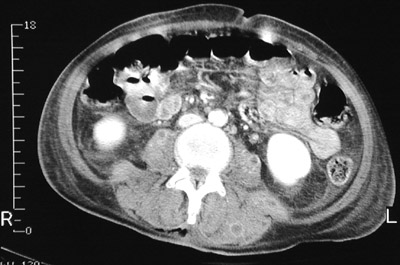

These pelvic CT scan views above and below reveal the presence of both larger abscesses as well as smaller abscesses with ring enhancement seen in paraspinal muscles.